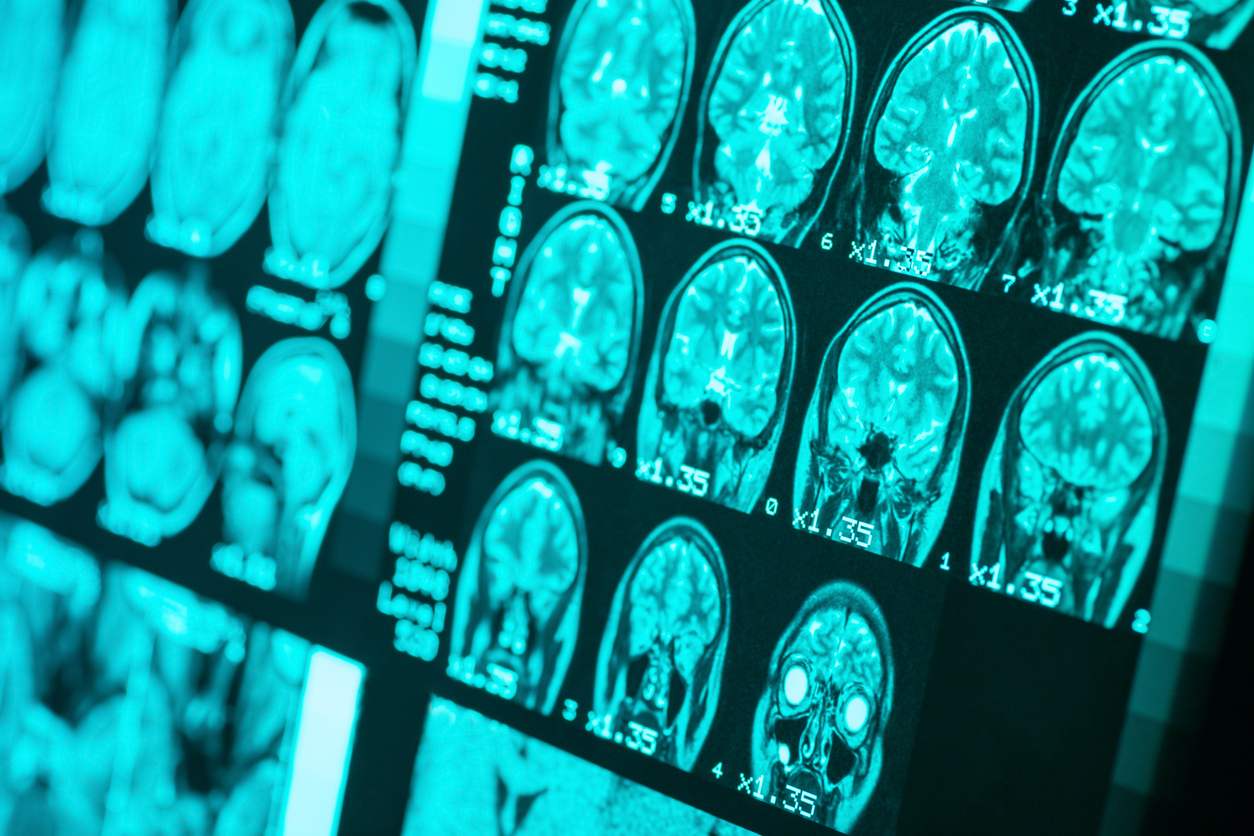

Le type de démence le plus courant est la maladie d'Alzheimer, qui représente 60 à 80% des cas. Découvrez ce que les recherches révèlent sur le diagnostic de la démence ainsi que les options de traitement pour les personnes âgées vivant avec une déficience cognitive.